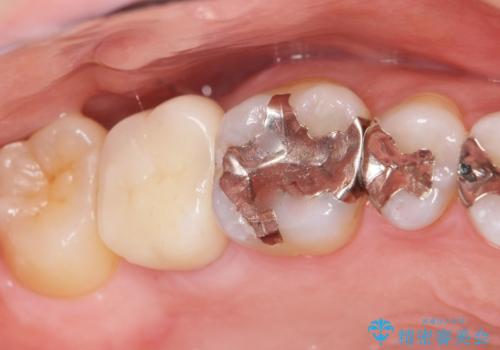

- 奥歯に違和感があることを主訴に来院された患者様です。

精査したところ、右上の奥歯(右上7)はう蝕が深く骨吸収も進行しており保存不可能な状態でした。

金属アレルギーの疑いがあり、インプラントも避けたいとの患者様のご希望により、親知らずを移植することにしました。